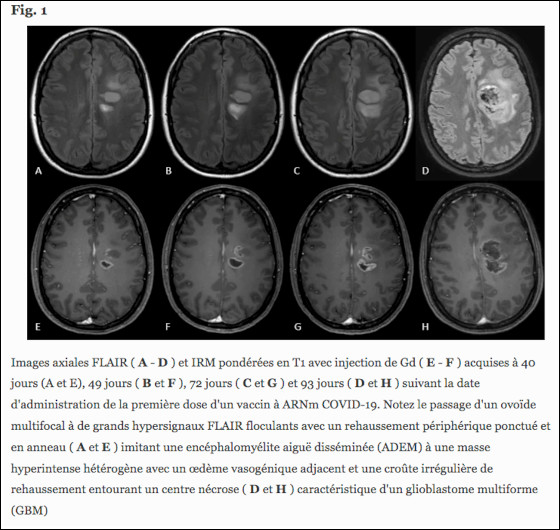

- Il existe bien au moins un cas, dans la littérature scientifique, et contrairement à ce qu’affirme le centre de pharmacovigilance de Lille, d’un cas de glioblastome suivant une vaccination anti-covid. En juillet 2021, des médecins décrivaient dans The Journal of Neurology le cas d’une femme de 31 ans ayant développé, dans les jours suivant sa vaccination covid, une encéphalomyélite aiguë disséminée, laquelle s’est révélée être ensuite un glioblastome.

Figure et légende (traduite) extraites de « Misinterpretation of glioblastoma as ADEM : potentially harmful consequences of over-diagnosis of covid-19 vaccine-associated adverse events », publié dans The Journal of Neurology, juillet 2021.